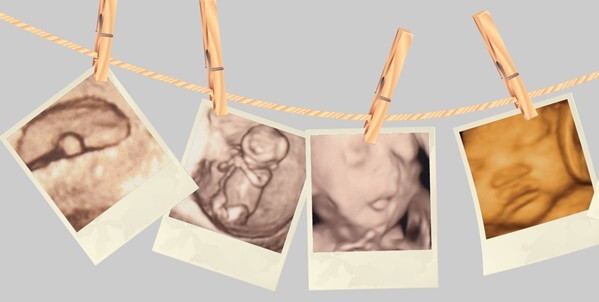

怀孕6个月采用四维彩超检查好吗?怀孕的女性关心的就是腹中宝宝的健康状况。福州台江医院医师指出:四维彩超就是一种可靠的产检项目,为广大孕妈妈减少很多担忧,能及时发现意外的问题并且能及时治疗。

怀孕6个月采用四维彩超检查好吗?福州台江医院妇科医师表示,怀孕6个月的孕妇完全是可以进行四维彩超的检查,主要可以检测出宝宝的动态情况,骨骼发育情况、是否心脏疾病情况等等。

四维彩色超声诊断仪能自动为胎儿进行宫内拍“写真”和动态录像,为众多的准妈妈增添了安心和情趣。

她们不再是仅仅感觉宝宝的呼吸和运动,而且可以亲眼目睹他们的一举一动和乖巧的秀容。更为重要的是,四维彩超能够多方位、多角度地观察宫内胎儿的生长发育情况,为早期诊断胎儿先天性体表畸形和先天性心脏疾病提供依据。

过去的B超设备只能检查胎儿的生理指标,而四维彩超还能对胎儿的体表进行检查,如唇裂,脊柱裂,大脑、肾、心脏、骨骼发育不良等,以便尽早的进行治疗。生个聪明健康的小宝宝,并且将宝宝的样子和动作制作成照片或VCD,让宝宝拥有完整的0岁相册,这已经不再是幻想。